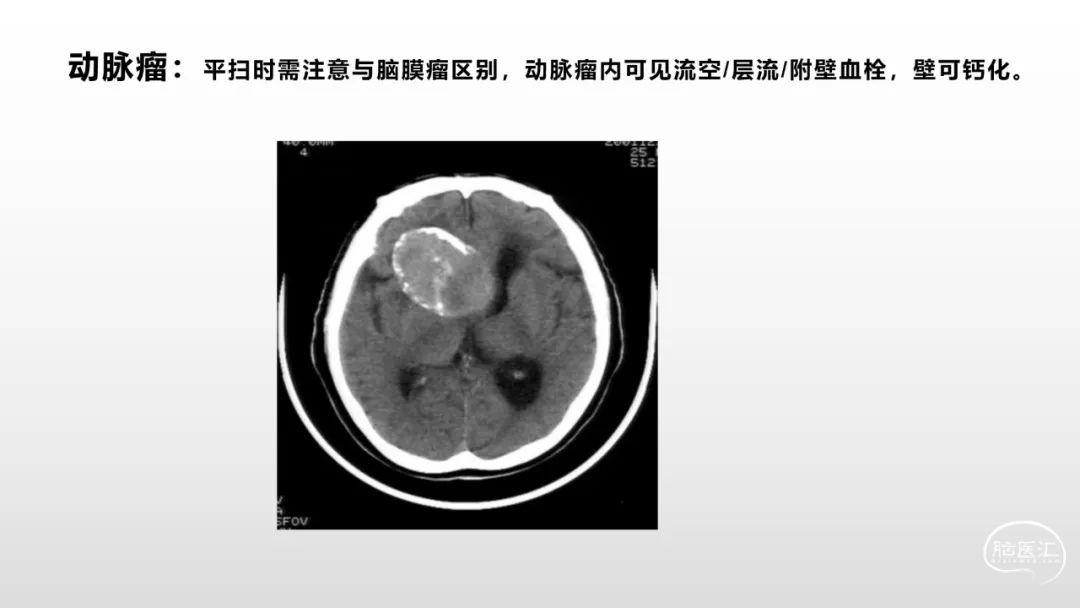

颅脑影像诊断基础知识讲座:脑膜病变